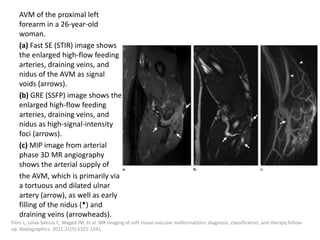

can then be treated with the sclerosant.

Müller-Wille R, Wildgruber M, Sadick M, Wohlgemuth WA. Vascular Anomalies (Part II): Interventional Therapy of Peripheral Vascular

Malformations [published online ahead of print, 2018 Feb 7]. Gefäßanomalien (Teil II): Interventionelle Therapie von peripheren

Gefäßmalformationen [published online ahead of print, 2018 Feb 7]. Rofo. 2018;10.1055/s-0044-101266.

Post-procedural care

Strict postoperative observation of the upper

airway is recommended after treatment of

patients with large cervical LMs.

Fever after injection of Picibanil can be treated

with paracetamol.